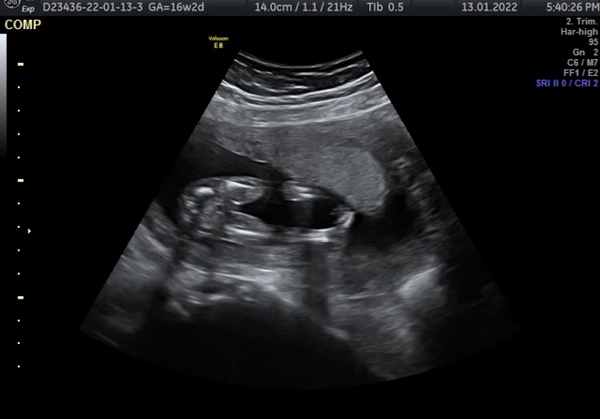

I had a 16 week scan the other day and we did the gender reveal today and I saw the ‘potty shot’. It doesn’t look like the potty shot I have seen before, and looks like it’s more of a side view. I’m just wondering what they have pointed out to be the penis has a line going down the middle and looks a lot bigger than other penis shots I’ve seen!! Is this normal? What is the line down the middle? They didn’t flag up any concerns at the scan!! Has anyone who had boy scans had something similar?

@Sweetieheart16 I’ve been in the same boat with my little girl! We’ve got 2 boys and know those potty shots well haha but with this one being a girl we had no idea what we were looking for your scan this made me feel a lot more comfortable though haha!